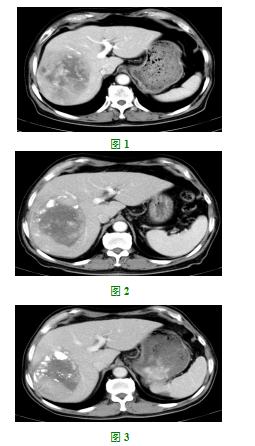

(见图2),有再次介入治疗指针,于2017年6月27日、2017年8月16日行第三次、第四次肝癌TACE治疗。四次介入结束后,患者于2017年10月23日来院复查增强CT:肝脏外缘凹凸不平,肝脏右叶见大小约9.8*7.0cm团块状影,边界部分不清,其内见部分碘油沉积,肿块大小较前对照略有缩小,增强后肿块内可见实性成分强化,并见大片坏死灶未见强化。肝左叶散在分布多个0.3-0.6cm低密度无明显强化结节影,部分系囊肿,部分性质待定。(见图3),AFP6.90ng/mL。患者目前肿瘤无增大,无解剖性肝叶切除指针,目前肿瘤区碘油沉积情况尚可,但肝左叶有散在结节,不排除肿瘤肝内转移可能,目前无继续介入治疗指针。结合我国自主研发的抗血管生成靶向药物甲磺酸阿帕替尼的临床研究,该药与治疗肝癌的甲苯磺酸索拉菲尼片作用机理类似,且有大量的临床数据支持在肝癌方面的应用,在充分征求患者及家属同意的情况下,于2017年10月25日开始口服艾坦(甲磺酸阿帕替尼)250mg po qd治疗,治疗期间患者出现尿蛋白++,血压增高,给予降血压治疗后恢复,治疗1月后于2017年11月27日行增强CT:较2017年10月23日CT片对照,肝脏肿块未见明显变化,肝左叶散在分布多个0.3-0.6cm低密度无明显强化结节影,部分系囊肿,部分性质待定。较前未见变化,随访。AFP4.90ng/mL。临床疗效评价为SD。继续口服该药。2018年01月08日行增强CT:肝脏外缘凹凸不平,肝脏右叶团块状影大小约10*7.0cm,边界部分不清,其内见部分碘油沉积,增强后肿块内可见实性成分强化,并见大片坏死灶未见强化。(见图4),患者肿瘤稍缩小,未达到PR,且一直有强化,肿瘤供血,经全科讨论后,制定B-TPS计划,于2018年01月23在CT引导下行放射性碘125粒子植入治疗,共植入碘125粒子30粒,肿瘤周边剂量为140Gy,粒子表面活度为0.8mCi。2018年02月27日复查增强CT提示为SD,故于2018年03月07日再次在CT引导下行放射性碘125粒子植入治疗,再次植入碘125粒子30粒,肿瘤周边剂量为140Gy,粒子表面活度为0.8mCi。患者继续口服艾坦,2018年07月02日复查增强CT:肝脏外缘僵硬,凹凸不平,肝右叶低密度影,大小约6.4*6.0cm,增强边缘显示清楚,动脉期见片状强化,静脉期亦见明显片状强化。提示部分肿瘤仍存在动脉供血。(见图5),临床疗效评价为PR。结合患者现在的情况,我们又组织科内讨论,于2018年07月20日又行TACE治疗一次,经上述治疗后患者继续口服艾坦治疗,至2018年12月03日复查增强CT临床疗效评价为SD。(见图6),患者一般状况佳,PS评分0分,无肝区疼痛等不适,肝功能正常。继续口服艾坦治疗中。